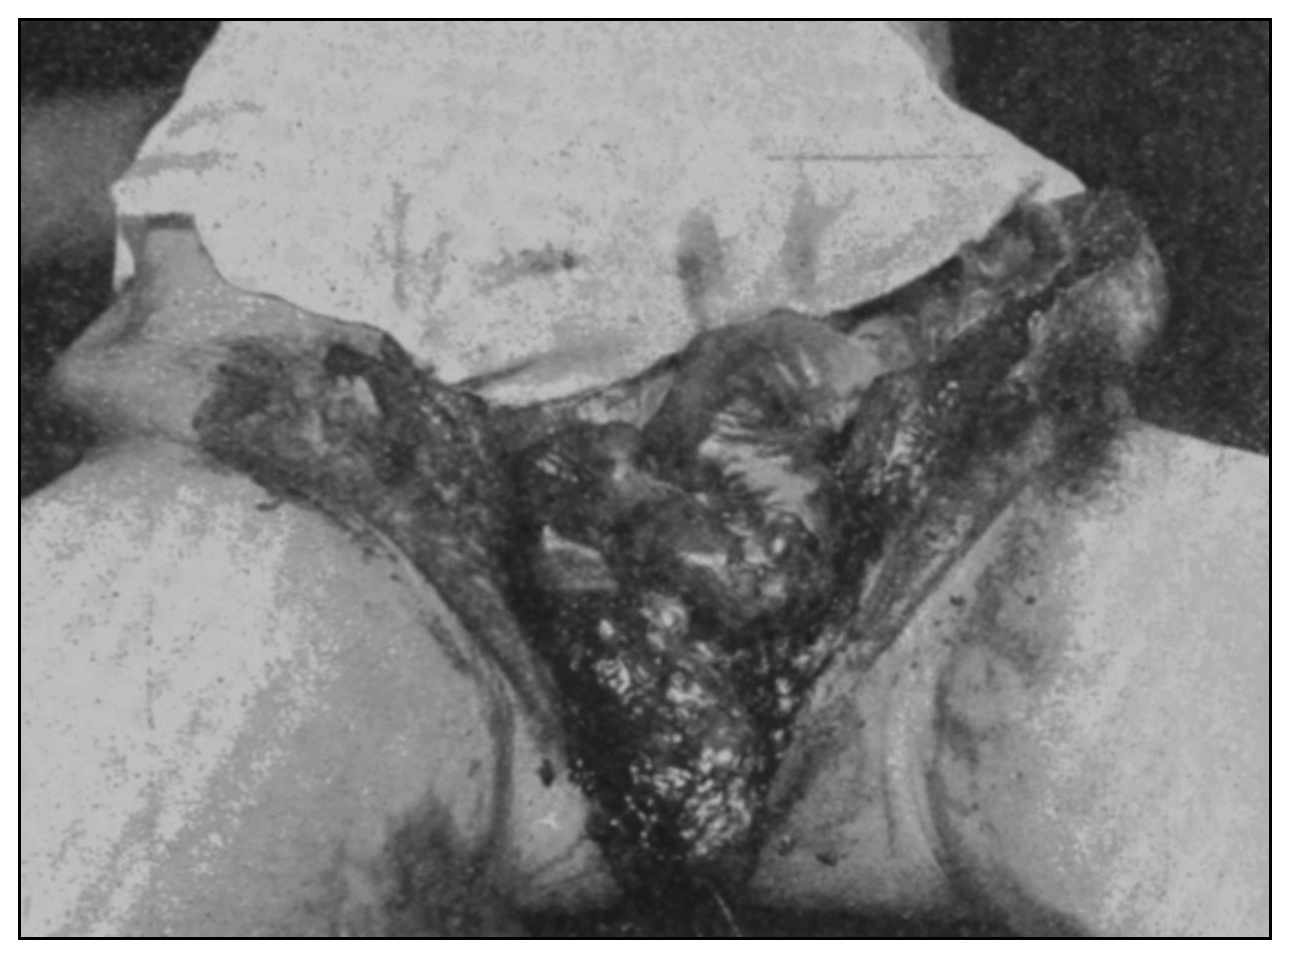

The photographic reproductions here published are documentary evidence of the existence of the obstructions under discussion. The sketch, Fig. 33, which was drawn from the valve while under the microscopic lens, exhibits the character of these obstructions and proves it that of a typic anatomic valve, and the absence of permanent bands of any other character in this organ is evidence that the semilunar valves and the so-called plica transversalis recti, Falten des Rectums, sphincter ani tertius, superior sphincter, and detrusor fecium muscles are one and the same thing and this thing is essentially a valve. It is most prominent when the gut is most distended.